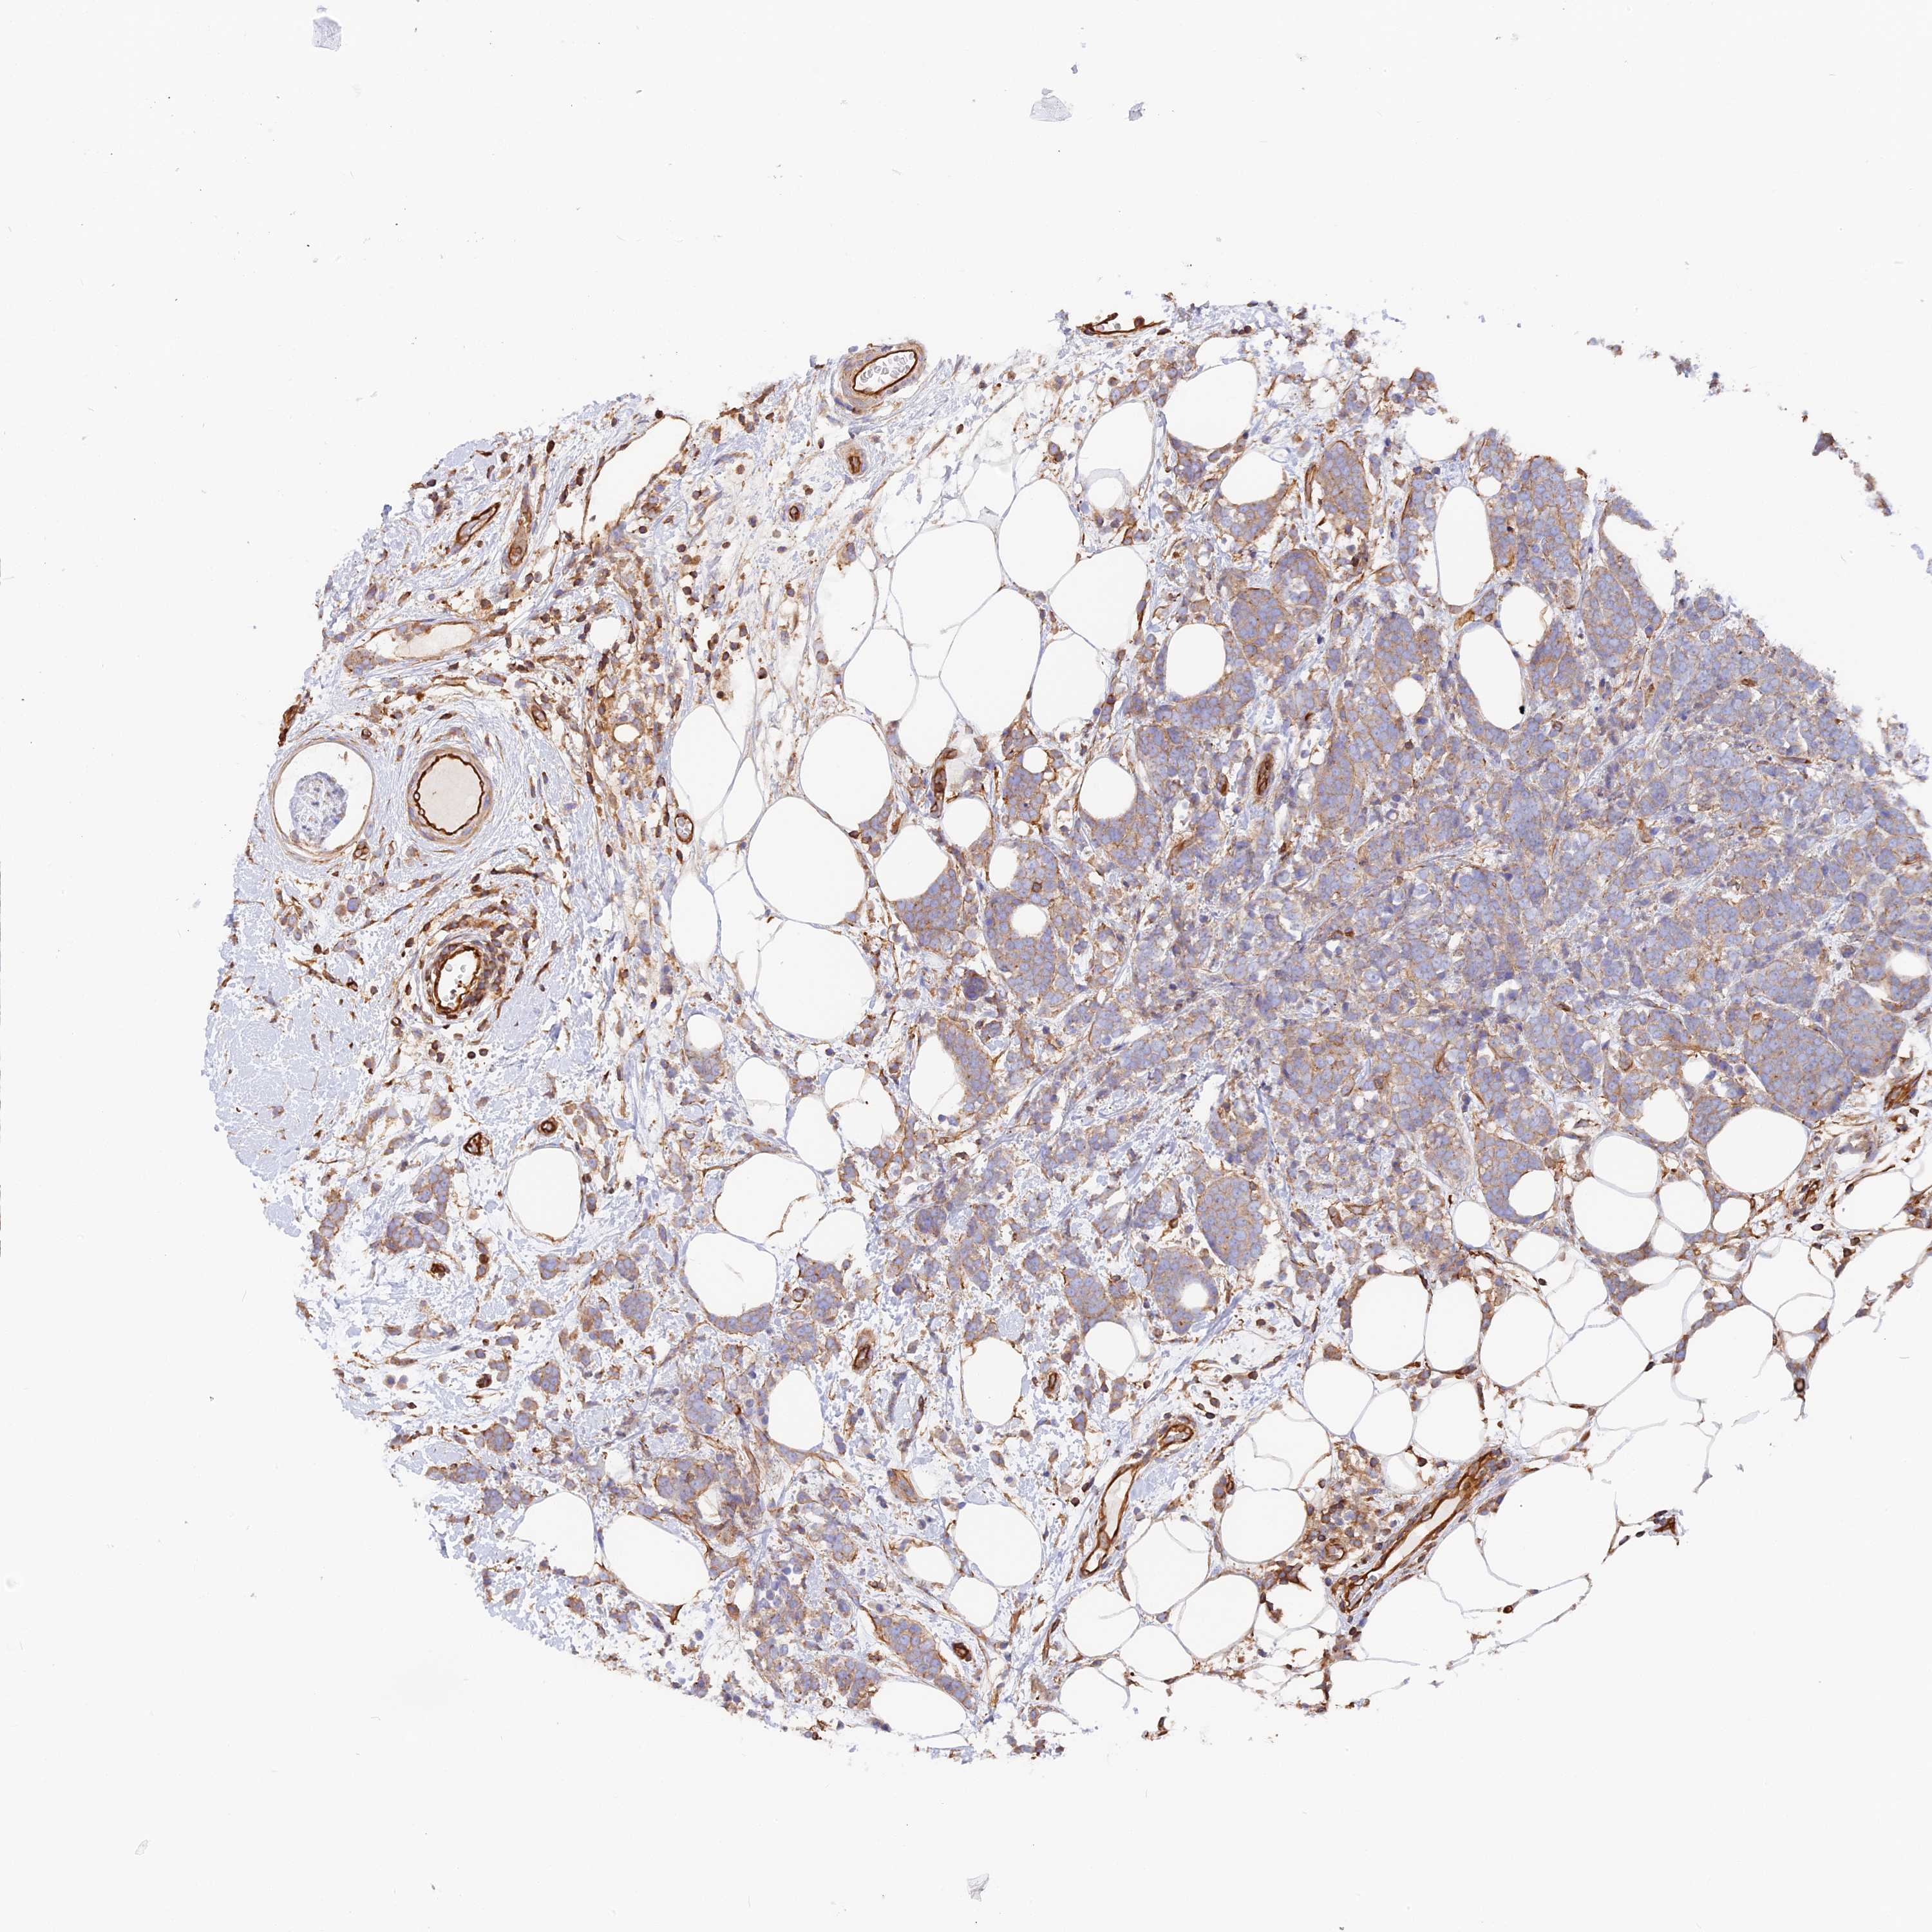

BRCA TCGA BRCA VALIDATION PROTEIN EXPRESSION